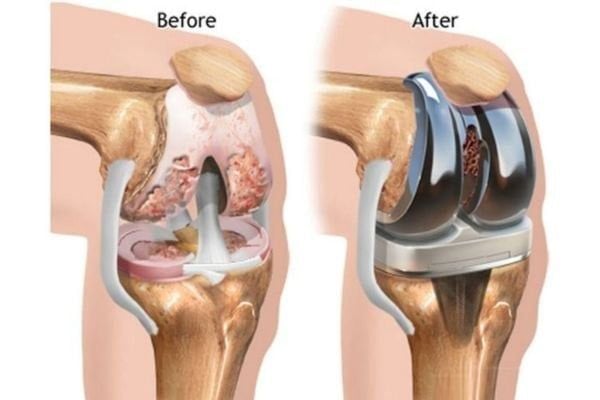

Phương pháp phổ biến nhất hiện nay là thay khớp gối toàn phần (Total Knee Replacement) – thay bề mặt khớp bị hư bằng vật liệu nhân tạo.

Kết quả sau phẫu thuật rất khả quan, đặc biệt khi người bệnh kết hợp phục hồi chức năng với vật lý trị liệu sau mổ.

Nếu bạn đang cân nhắc phẫu thuật, nên đến khám vật lý trị liệu trước khi mổ để chuẩn bị các bài tập phục hồi sớm – vì bắt đầu sớm giúp kết quả tốt hơn.

Ảnh: Điều trị với phương pháp phổ biến nhất hiện nay là thay khớp gối toàn phần (Total Knee Replacement) – thay bề mặt khớp bị hư bằng vật liệu nhân tạo